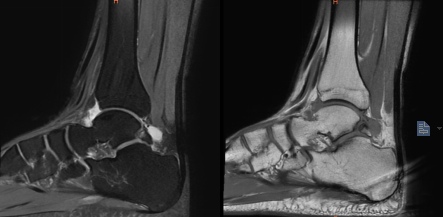

近日,重庆医科大学附属璧山医院(重庆市璧山区人民医院)手足外科团队完成一例左上肢淋巴水肿超显微外科手术。该手术的成功开展,标志着医院在该领域实现新的突破。